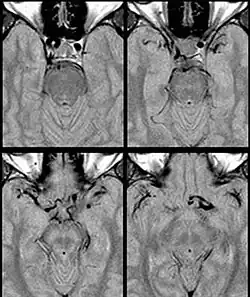

Fig. 1: Dolichoectasia of the suprasellar segment of the left internal carotid artery with compression of the optic chiasm

Internal carotid artery dolichoectasia is particularly interesting because the artery normally already contains one hairpin turn. Seen in an MRI as two individual arteries at this hairpin, a carotid artery dolichoectasia can progress so far as to produce a second hairpin turn and appear as three individual arteries on an MRI. In the case of a dolichoectasia of the Internal Carotid Artery (ICD), the pathogenesis is primarily related to compression of the optic nerves at the optic chiasma (see Fig. 1 and 2).